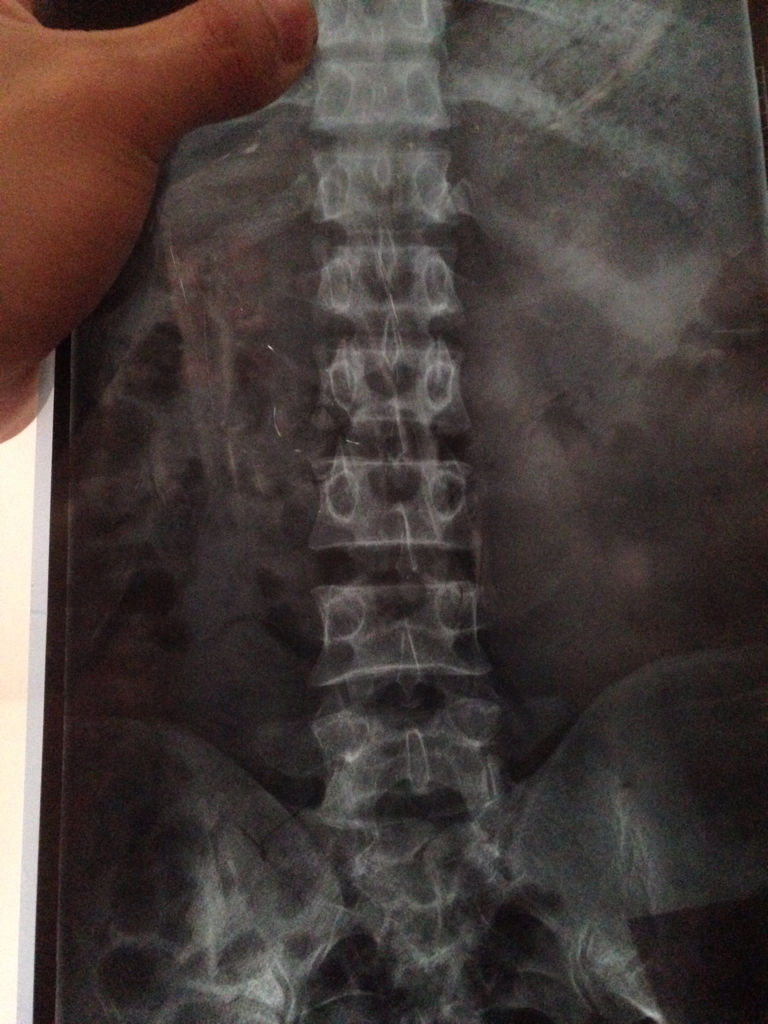

问:求大神 帮我看看 腰伤 原因蹲在地上10分钟 一下起来 就腰痛 腰就